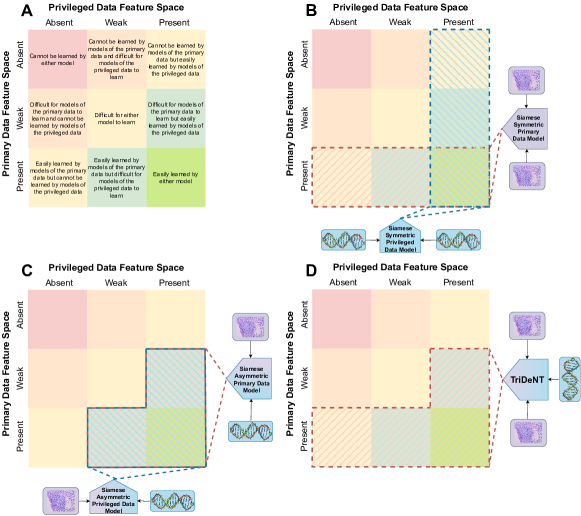

Self-supervised LUPI training has been shown to be a highly effective method of improving the performance of models whose privileged data contains more task-relevant information than the primary data [19, 20]. These methods are designed to minimise the difference between the representations of each input by mapping all embeddings into a shared latent space (joint embedding) [21]. However, in the case where we are only interested in the output of one branch, this can be restrictive. For example, if a feature is not shared between both inputs, these methods will neglect it, leading to worse performance [19] (Figure 1(a), see Sections 4.3 and 4). This was apparent in [20], where, despite impressive retrieval performance, the proposed joint embedding model significantly underperformed supervised models on classification tasks, implying that important features were neglected in the primary domain. In this work we present TriDeNT ♆ (Figure 1(b), Section 4.4), a new method designed to enable features which are only present in the primary data to be learned in addition to those shared between inputs. The main contributions of this work are:

Using standard computational pathology tasks, we find that the previous state of the art – standard Siamese self-supervised joint embedding architectures (e.g. [20]) – embeds only information shared between views, meaning performance is reduced where not all task-relevant information is present in the privileged input;

As Table 1 shows, we find that TriDeNT ♆ is also highly effective on all tasks compared to the unprivileged Siamese baseline. As there is more information in the privileged paired data, the privileged baseline is considerably higher for this task. Despite this, TriDeNT ♆ still outperforms both comparable baselines on all tasks but one, achieving improvements of up to 25.1% compared to the unprivileged baseline and up to 5.8% compared to the privileged baseline. There is only a single task where TriDeNT ♆ does not improve performance: evaluation on the PanNuke dataset of a model trained with the VICReg loss, performing 1.6% less than the privileged baseline. The brightfield IHC stains contain considerably more task-relevant information for cell segmentation, so this is unsurprising. This effect can be understood visually as the IHC ‘weak’ quadrant in Figure 1(a) being very narrow and containing very few features. Most task-relevant features are strongly present in the IHC and therefore there is less to be gained by adding the few missing weak features.

Despite the apparent advantage of providing privileged information to a model, it has been shown that training with privileged information does not satisfy a no-harm guarantee [50]. This can be due to a variety of factors, such as because estimating properties of the privileged information can be more difficult than estimating the same properties of the primary data. It was shown in [19] that Siamese LUPI leads to improved performance on tasks where the privileged input contains more task-relevant information than the primary input, e.g., a low-resolution image paired with a high-resolution image. However, it is also observed that if the privileged input contains less task-relevant information, it can reduce performance. This is because mapping both inputs into the same latent space causes task-relevant information in the primary input to be lost if it is not shared between branches, as is visualised in Figure 1(a). Consequently, non-LUPI learning can lead to better performance in these scenarios, despite the loss of additional task-relevant information which could be gained from an privileged input.

As Siamese joint-embedding models minimise the difference between representations in the shared embedding space, any features which are not shared between branches will be neglected. There is no way to predict a feature in the privileged input from the primary input if no information exists about that feature in the primary input. On the other hand, features which are weakly present in the primary input but strongly present in the privileged input may be learned, as there is a strong supervisory signal from the privileged data. In the non-LUPI setting (Siamese learning without privileged inputs), such features are unlikely to be learned due to the absence of the strong signal from the privileged input. Formally, following [51], we consider features which have variance that is nonzero but lower than the augmentation regime to be weakly present, and those with greater variance than the augmentation regime to be strongly present.

For an intuitive understanding of the method, it is helpful to consider the representation of each branch as a supervisory signal for the others. Our model can therefore be considered a multi-objective setting, where the primary encoder aims to balance the information extracted from each augmentation of which is shared with , and that which is shared with the other augmentation of . In turn, the supervisory signals for are and , and consequently they will only extract features which can also be found in . In our typical setting, this corresponds to balancing information which is only weakly present in the primary input , but strongly present in the privileged input , with information which is strongly present in primary input . The result of this trade-off is that privileged features with a strong supervisory signal from and are learned, but primary features with a strong supervisory signal from from are also learned. This is in contrast to the dichotomy between only learning strong features or only learning shared features presented by the standard 2-branch approaches.